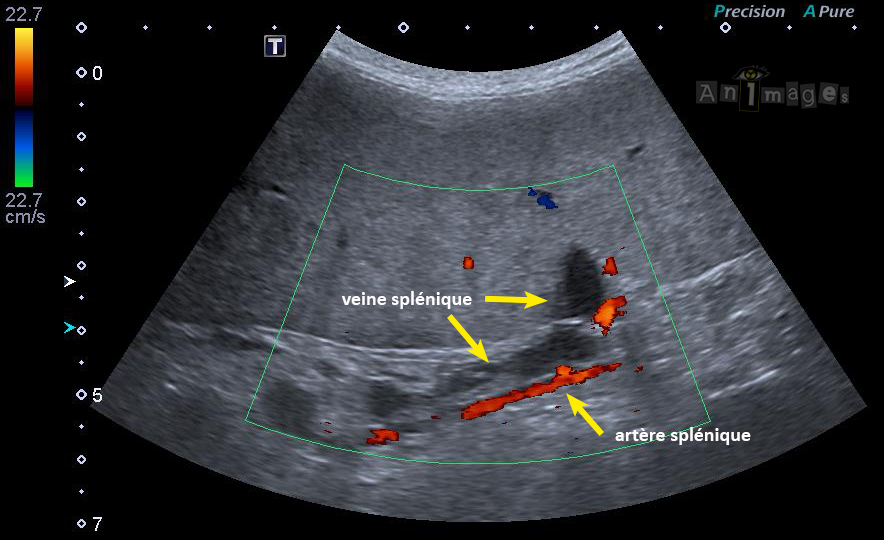

Nos spécialistes en imagerie médicale vétérinaire parcourent le grand Montréal à chaque semaine pour des échographies dans les cliniques vétérinaires.

Afin de mieux répondre à la demande croissante et à mieux s’organiser, nous demandons dorénavant aux cliniques de remplir ce formulaire pour réserver une place: https://form.jotform.com/202334013106032.

Nos techniciennes pourront alors rapidement vous contacter pour vous proposer une date.

Sachez que nos équipes suivent un protocole sanitaire stricte pour limiter la propagation de la COVID-19.

Pour toute question sur nos services mobiles, les employés des cliniques vétérinaires peuvent nous contacter à echomobile@animages.ca ou par téléphone au 514-397-9352.

Dre Mylène Auger a obtenu son diplôme de vétérinaire de la Faculté de Médecine Vétérinaire de l’Université de Montréal en 2008, et a par la suite complété un internat à la même institution en 2009. Suivant quelques années de travail en pratique générale des animaux de compagnie, son intérêt marqué pour l’échographie abdominale l’a amené à compléter un internat spécialisé en imagerie médicale au Centre Vétérinaire Laval, sous la supervision du Dr. Éric Norman Carmel, en 2016. Elle a ensuite complété un programme de résidence en imagerie médicale à l’University of Tennessee en 2020, travaillant comme clinicienne en imagerie à cette institution lors de la quatrième année du programme de résidence, et elle obtient la certification de l’American College of Veterinary Radiology en 2019. Elle fait maintenant partie de l’équipe Animages et partage son temps professionnel entre le Centre Vétérinaire Rive-Sud, le Centre Vétérinaire Laval, l’échographie mobile, le Centre Hospitalier Universitaire Vétérinaire (CHUV) de la Faculté de Médecine Vétérinaire à St-Hyacinthe, et la téléradiologie.